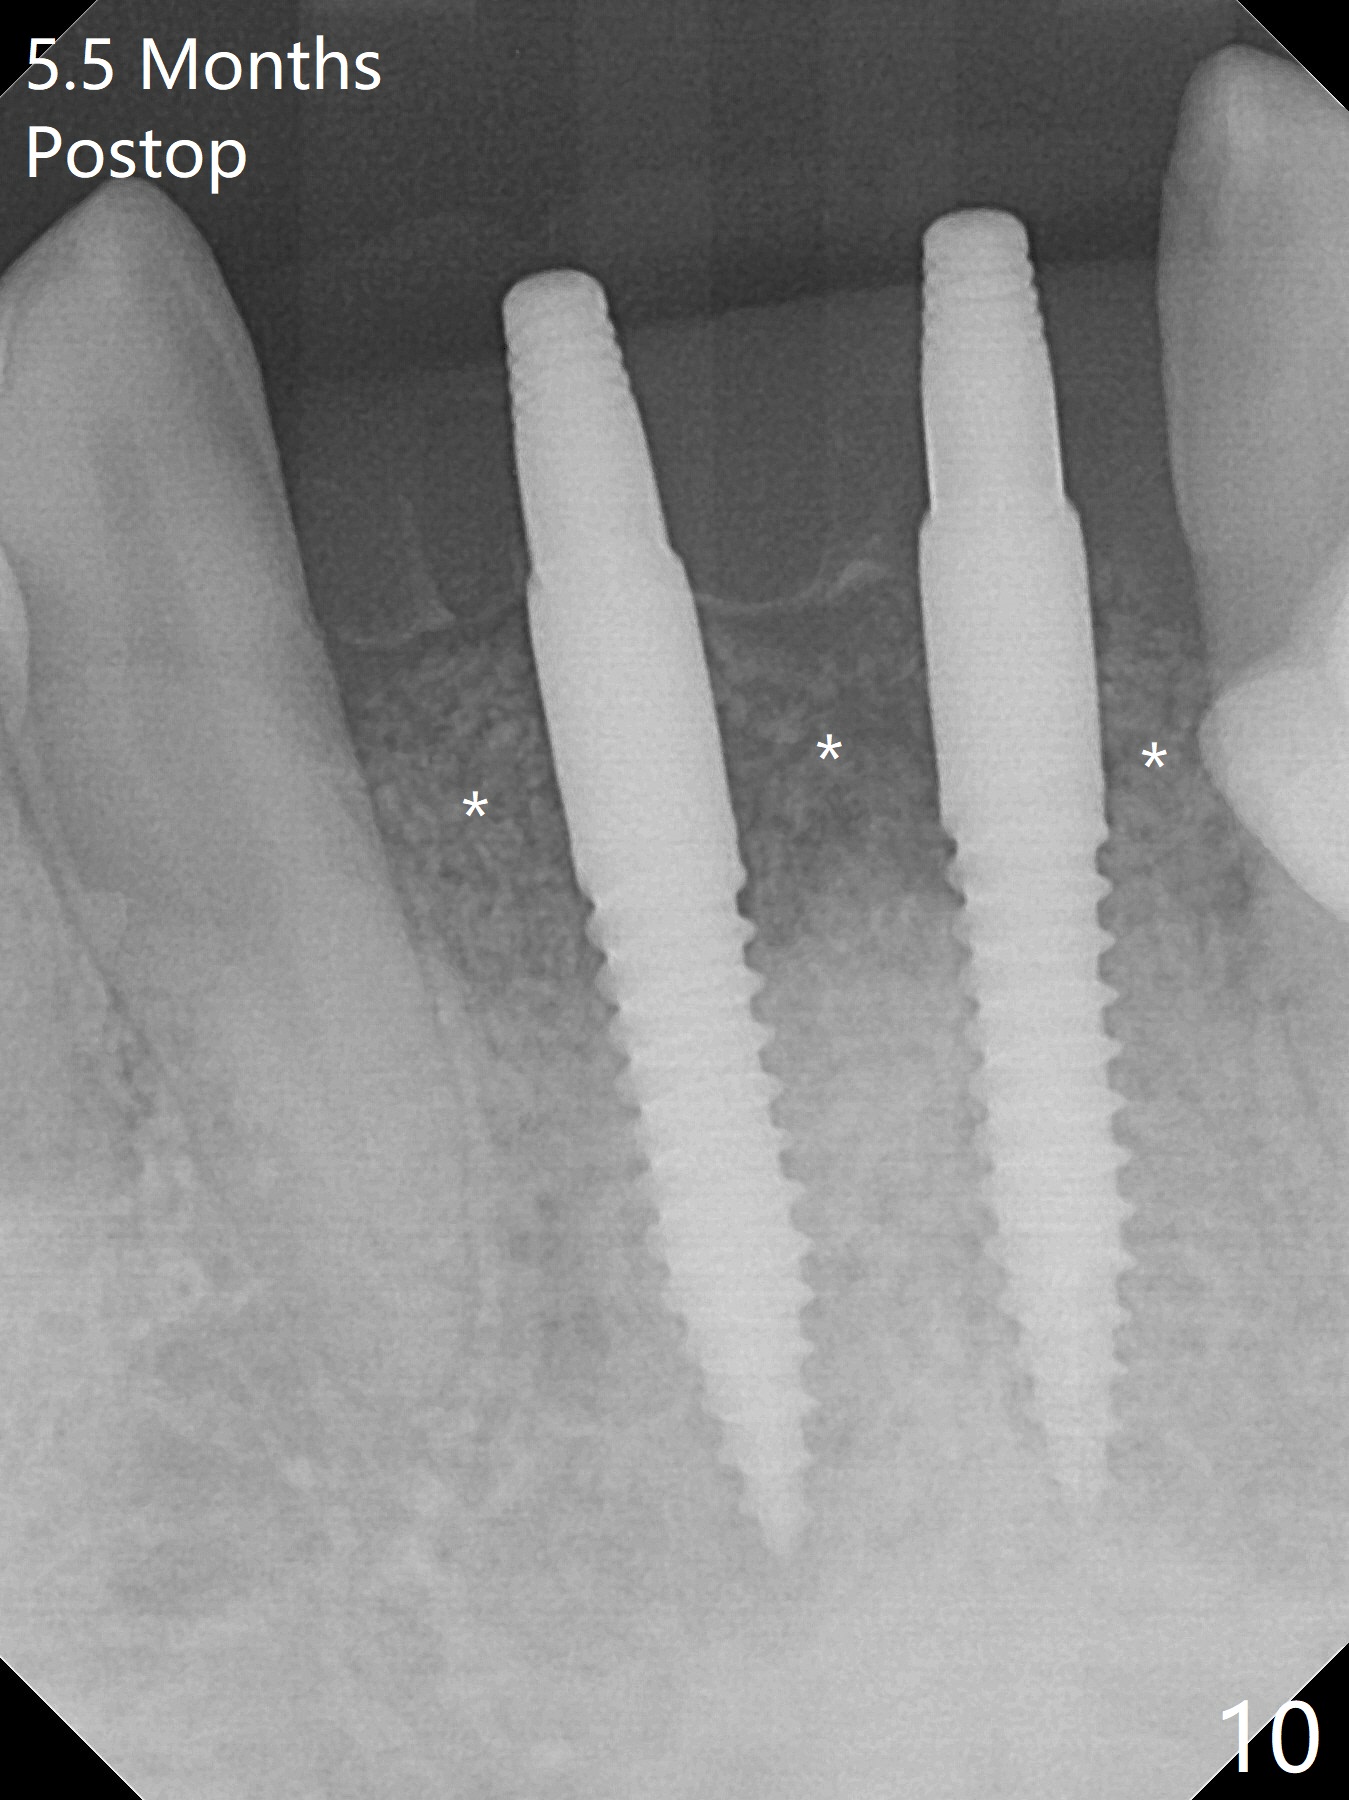

After extraction of 4 of the lower incisors, there are basically 2 sockets (#23/24 and 25/26), separated by the apparently midline bone (Fig.1 red line).  In spite of using Lindamann bur to move the 25/26 osteotomy mesially, a 3x14(2) mm dummy implant remains close to the tooth #27 (Fig.2).  The terminal branch of the Incisive Canal (<) is located between the lateral and central incisors.  A de novo osteotomy (Fig.3 (1.5 mm drill)) is made mesial to the original one (O).  While the 3x14(2) mm dummy implant is incompletely placed at #25/26, a 3x14(4) mm 1-piece one is placed at #23/24 (Fig.4).  Finally the same implant is placed at #25/26 with placement of mineralized cortical/cancellous bone (Fig.5 *).  When the large sockets are sutured, the supraerupted teeth #7-9 touch the lower gingiva (Fig.6).  The incisal edge is reduced for clearance (Fig.7).  Periodontal dressing is less likely to be dislodged with the incisal edge reduction (Fig.8,9).  A provisional FPD is fabricated 1 week postop.  Hard (Fig.10) and soft (Fig.11,12) tissues heal 5.5 months postop.  The patient returns for crown cementation 3 months post impression (9 months postop, Fig.13,14).